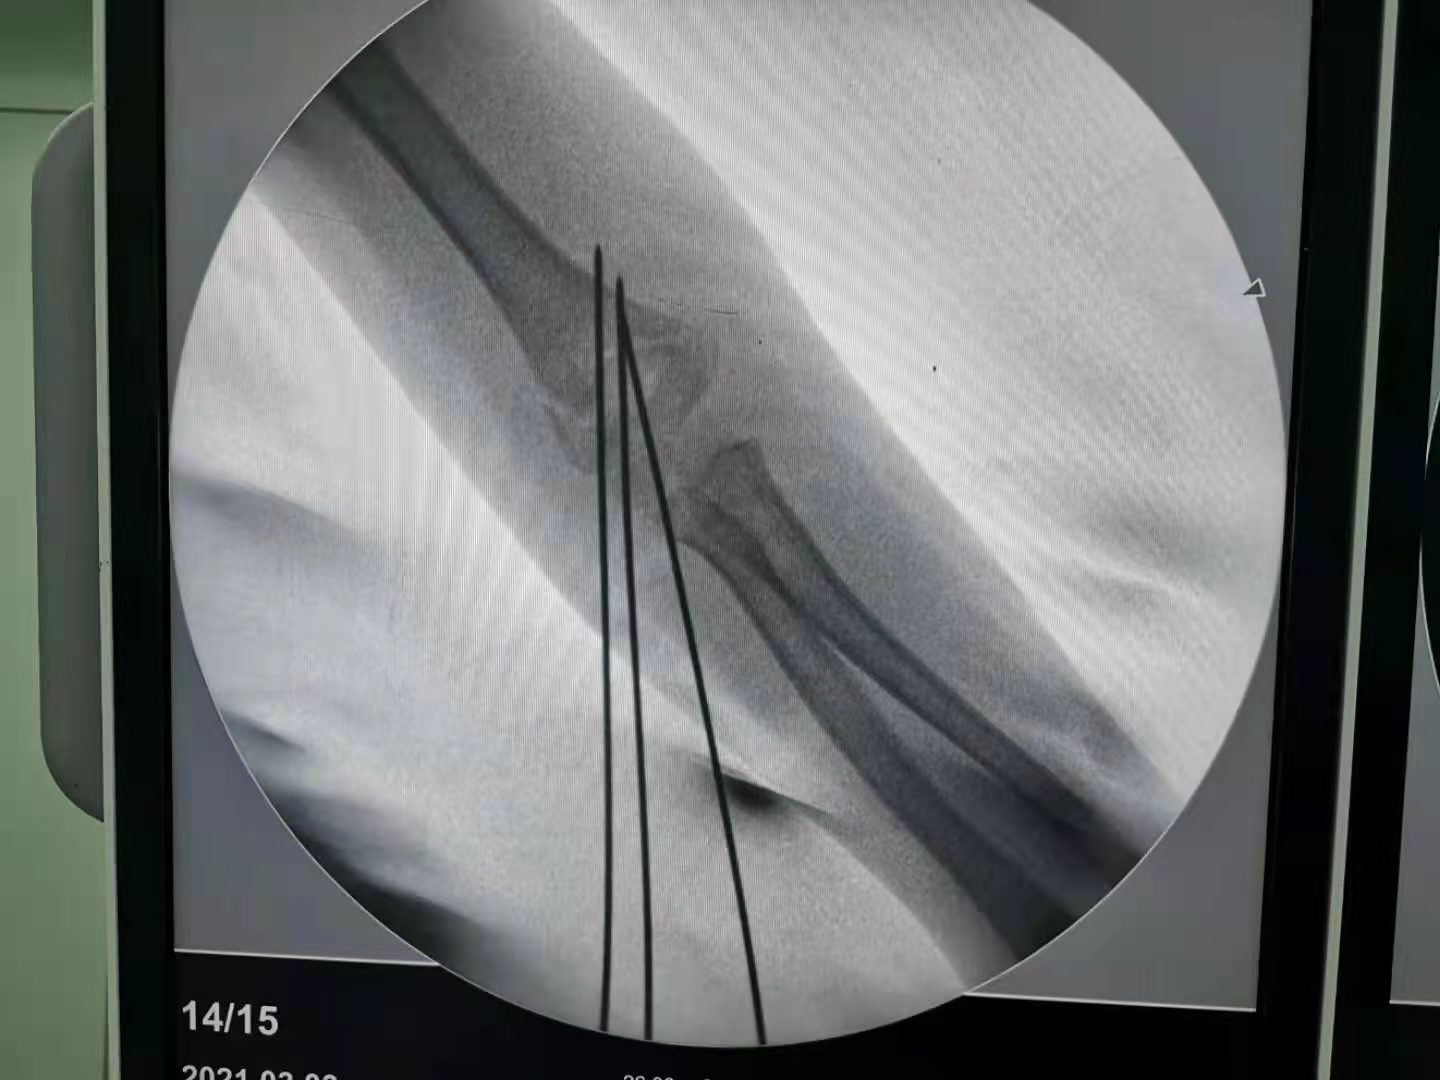

为了不断地满足患者的美观需求,同时医疗技术的不断提高,不需开刀不留瘢痕治疗儿童肱骨髁上骨折不再是梦。对于肱骨髁上骨折,我们的手术方法是“闭合复位经皮穿针固定”,是先进的微创手术方法,绝大多数不需要开刀,损伤很小,没有切口也不会留下瘢痕。只有非常少的情况下,例如开放性骨折或者骨折不可复位才可能需要做切开复位。